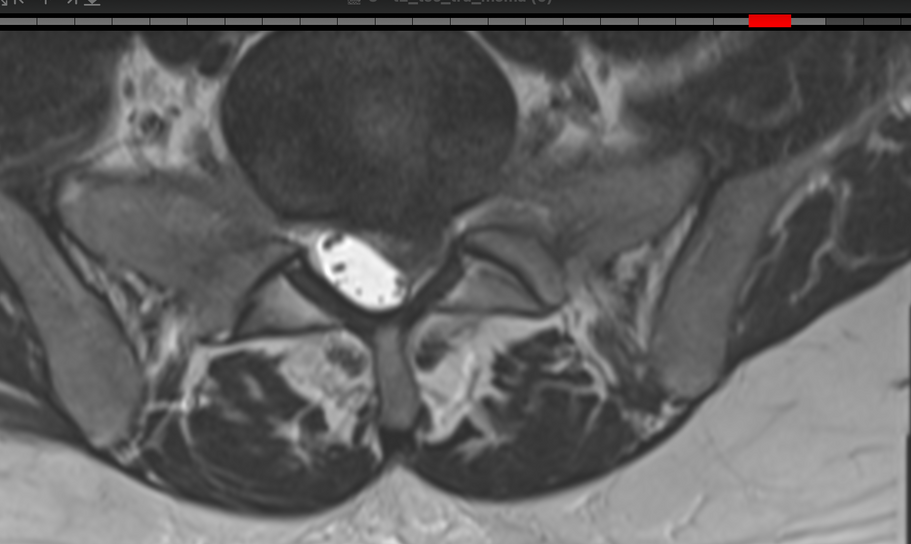

Patiente de 32 ans. Symptômes : Lombosciatique bilatérale invalidante, associée à des paresthésies et à une légère sensation de faiblesse musculaire lors de la dorsiflexion des pieds. Diagnostic : Hernie discale L5-S1 importante.